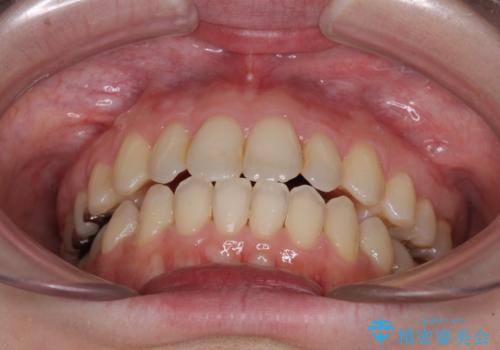

- 前歯のデコボコを気にして来院された患者様です。

下顎が骨格的にずれており、上下正中を合わせることは難しいことが予想されたため、デコボコの解消を主目的として、ワイヤー矯正を行うこととしました。